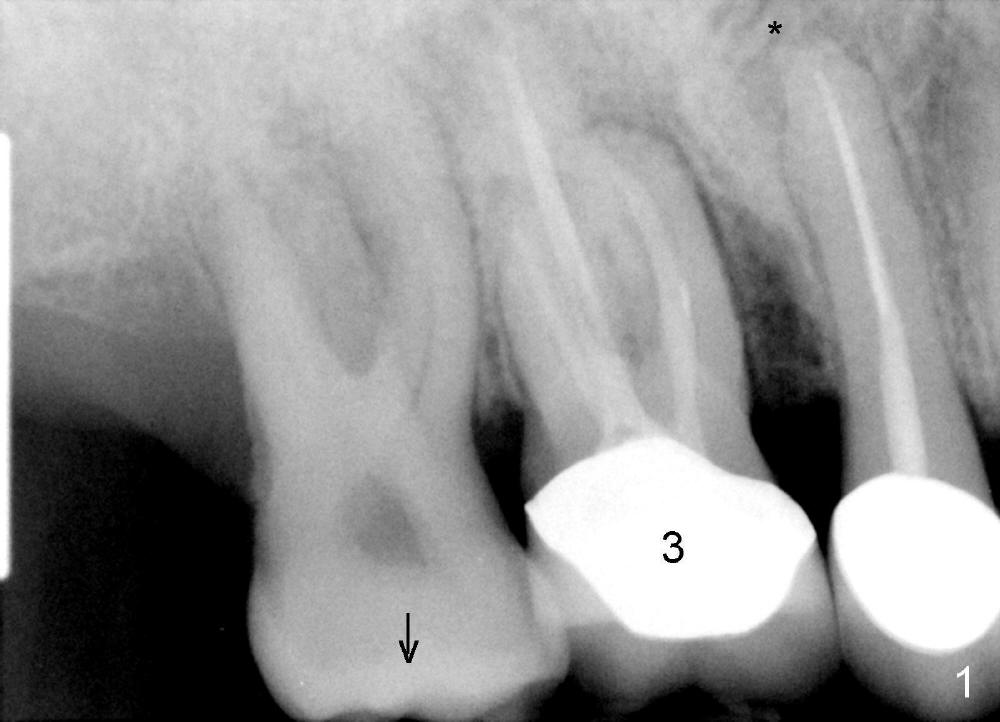

A 51-year-old man requests taking care of hemorrhage and odor associated with the tooth #3 (Fig.1). Due to religious and financial issues, the neighboring teeth will be treated later (supraeruption of #2 (arrow) and periapical radiolucency of #4 (*)). CBCT reveals that the septum of #3 is large enough to hold 4.5 mm implant (Fig.2). In fact osteotomy is created as planned in the septum using drills and taps (Fig.3 after removing 4.5x20 mm tap). Primary stability is obtained with a 4.5x20 mm implant (> 60 Ncm, Fig.4). The gap (*) is bone grafted; an abutment is placed (Fig.5 A); an immediate provisional is fabricated and cemented to cover the socket (Fig.6 P). When the socket heals in 3 weeks postop, the provisional and the abutment are removed for easy oral hygiene. Bone regenerates around the implant 3.5 months postop (Fig.7 *), but the 2nd molar has shifted mesially (arrow), presenting a restoration challenge.